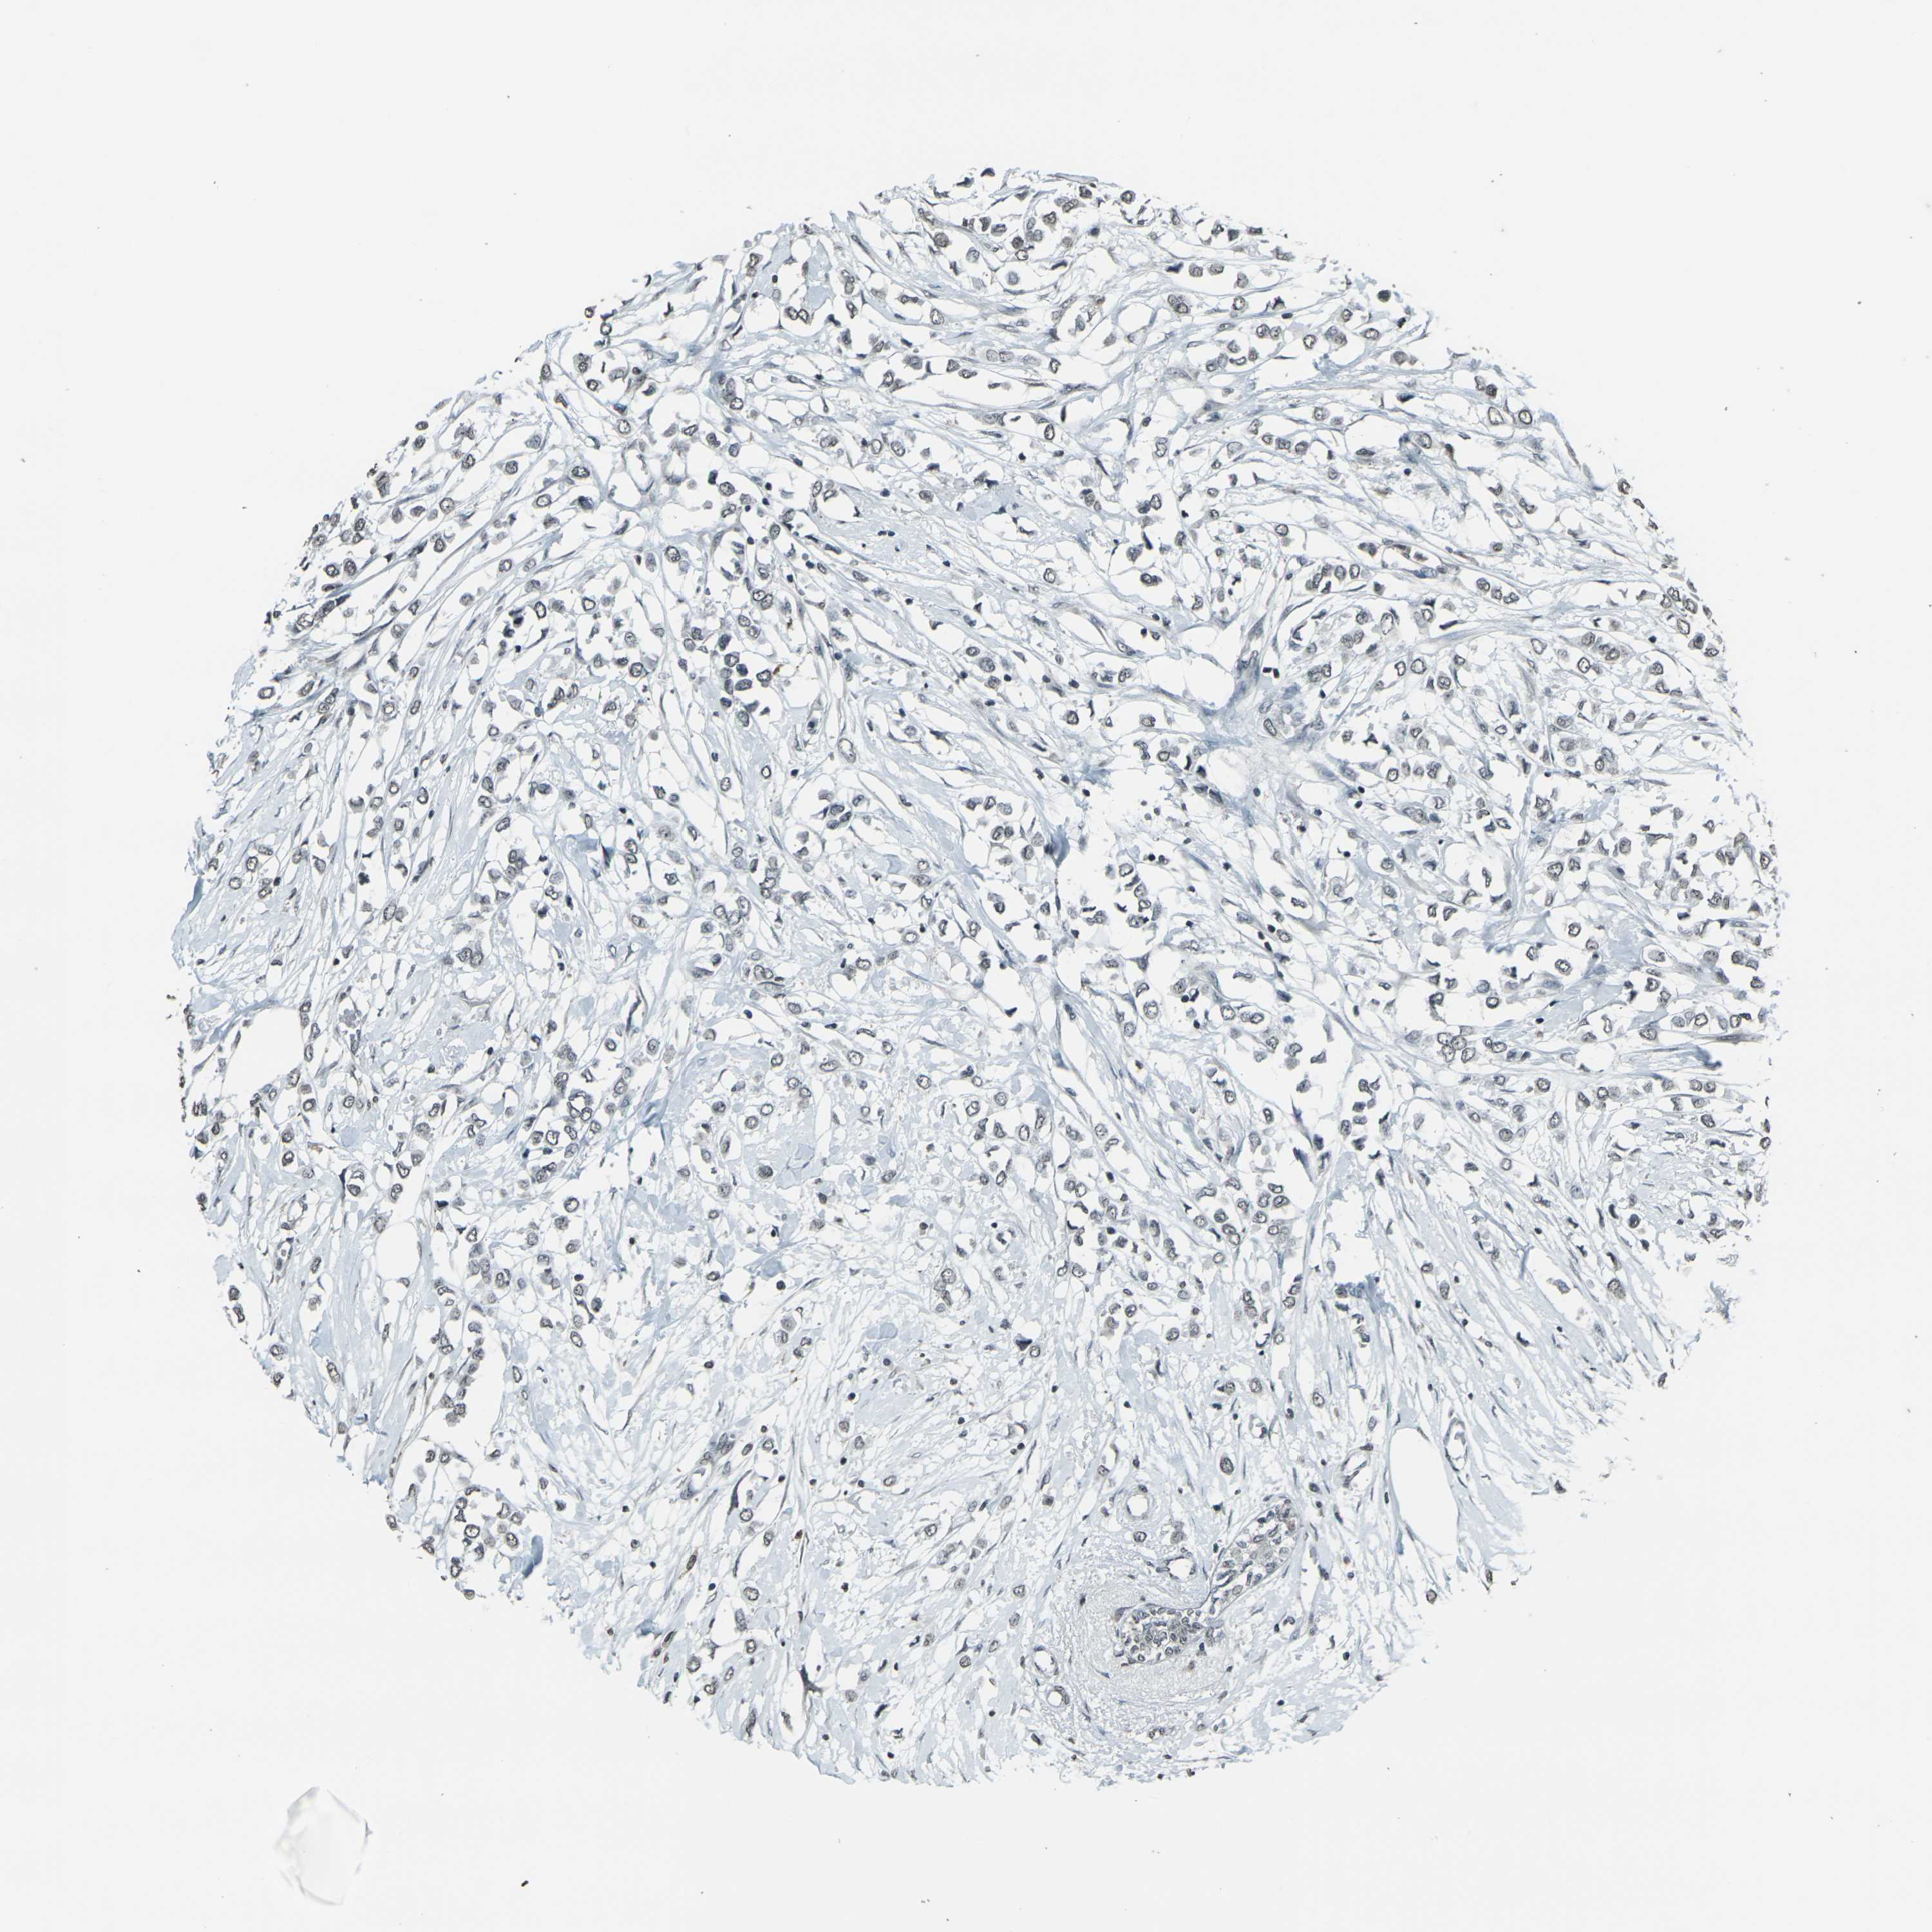

CANCER BREAST CANCER Show tissue menu

BRCA TCGA BRCA VALIDATION PROTEIN EXPRESSION